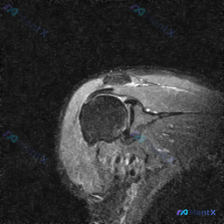

今天碰到一个有意思的病例:临床主诉怀疑肩部软组织有积液,但给到的只有一张肩部MRI T2加权轴位图像,我们一起来整理一下分析思路。

临床怀疑「肩部软组织积液」,提供单张肩部MRI T2序列轴位图像

- 图像质量:信噪比较低,有一定伪影,主要解剖结构可辨认

- 影像读片结果:

- 骨骼关节:肱骨头形态完整,关节对位好,前方盂唇形态信号正常,关节间隙无异常积液

- 肩袖肌腱:肩胛下肌、冈上/冈下肌腱附着处无连续性中断,无全层撕裂、明显水肿,周围肌肉无萎缩脂肪浸润

- 其他结构:肱二头肌长头腱走行正常无脱位,腱鞘无异常积液,周围软组织无肿块异常信号

- 核心矛盾:临床怀疑软组织积液,但这张图像上完全没看到明确的异常积液,也没有发现主要的结构性损伤

首先梳理确定的结论:在这张图像的扫描层面和现有质量下,确实没有看到明确的肩袖全层撕裂、盂唇撕裂、肱二头肌长头腱脱位,也没有看到明显的异常高信号积液。